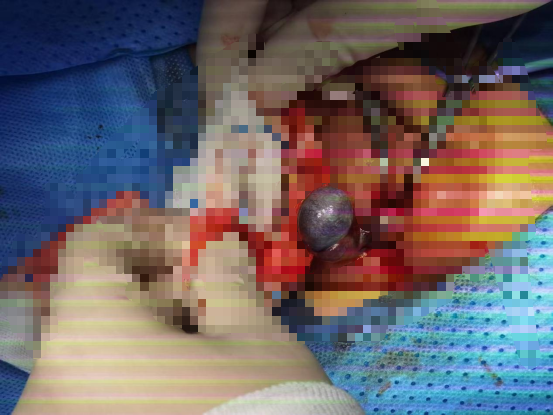

当田帅主任切开乐乐的阴囊时,心一下子沉了下去,乐乐的左侧睾丸已经变成了黑紫色,附睾发育也存在异常,尾部和睾丸完全分离。

田帅主任小心翼翼地把扭转的精索复位,然后耐心观察了30分钟,可睾丸的颜色丝毫没有好转……

为了进一步确认,医生在睾丸上切开了一个0.2cm的小口,预想中鲜红色的血液没有流出,只有少量暗红色的淤血——这意味着睾丸已经彻底坏死。